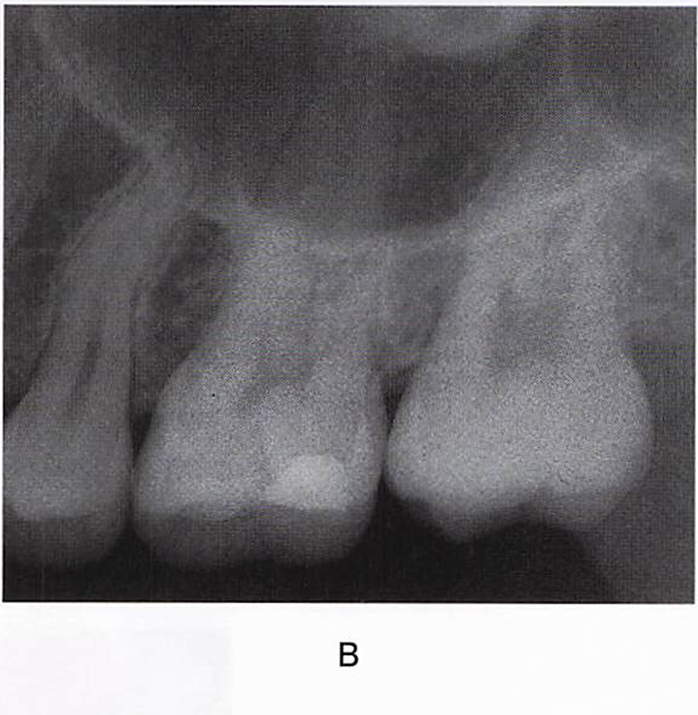

午後-95

60歳の男性。上顎左側第一大臼歯が水にしみることを主訴として来院した。10年前に修復処置を受けたという。コンポジットレジン修復を行うことになった。初診時の口腔内写真(A)、エックス線画像(B)および回転切削器具の写真を別に示す。 最初に使用するのはどれか。1つ選べ。

a. ①

b. ②

c. ③

d. ④

解答を見る

a